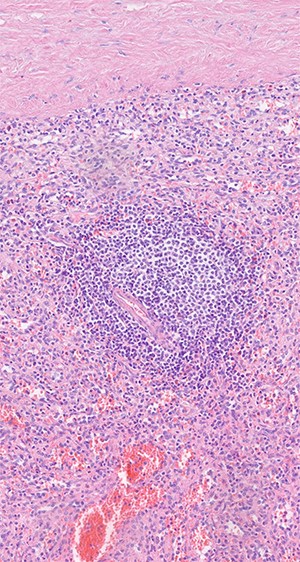

Histologic examination shows red and white pulp as main compartments of the spleen; B-cell follicle with geminal center, mantle- and marginal-zone; perifollicular red pulp with sinus; HE×20.

was located in the left upper quadrant of the abdomen, nearly adherent to the stomach and a moderate variceal conglomeration in the fundus of the stomach (Fig. 2). Liver cirrhosis or portal vein occlusion and other inflammatory or malignant diseases could be excluded from CT imaging. In addition, a CT scan was able to show clearly that the arterial blood supply of the accessory spleen is derived from the short gastric arteries. Splenic artery and vein could not be delineated. The patient was subsequently presented to our Department of Visceral Surgery. We decided to perform laparoscopic accessory splenectomy to relief the regional hypertension of the short gastric veins. In the operation room, the patient was positioned in right semi-decubitus position. One 12 mm Trocar, two 11 mm Trocars and on 5 mm Trocar were inserted in the left upper quadrant. The accessory spleen was extremely adherent to the diaphragm and retroperitoneal tissue (Fig. 3). After transection of the short gastric vessels with the vessel sealer (Ligasure™, Medtronic, Germany), the spleen was mobilized and removed (Fig. 4). Patient’s postoperative course was completely uneventful, and he was discharged in good health condition on the seventh postoperative day. The diagnosis was confirmed by immunohistologic examination (Fig. 5).